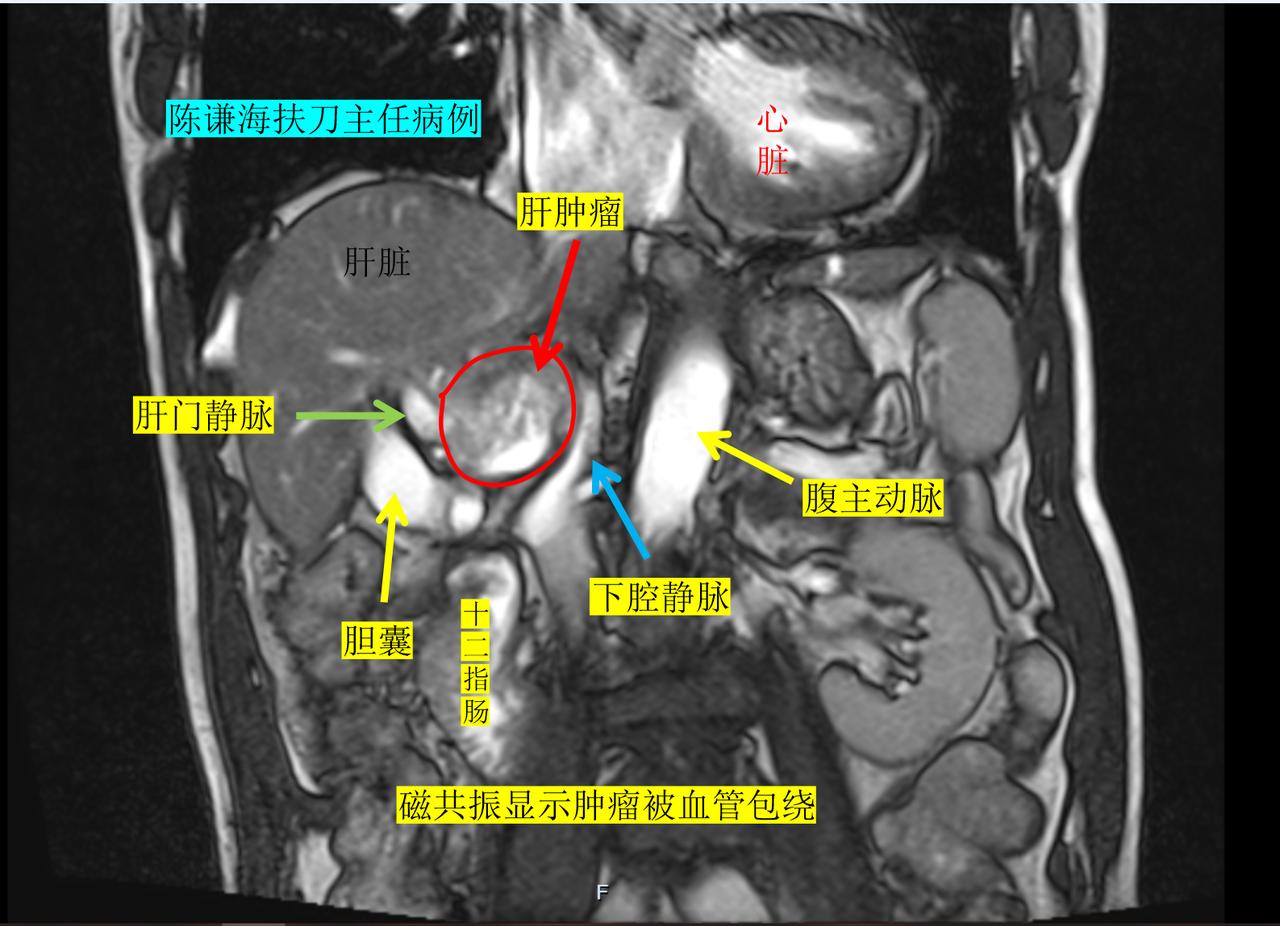

这是我们上周才治疗的一名晚期肝癌患者,病人74岁,来自江西,患者确诊原发性肝癌后,在当地做了介入治疗,射频消融治疗等综合治疗后,肿瘤有残留复发。 现在复查增强磁共振显示肿瘤紧邻门静脉、下腔静脉,旁边是胆囊,靠近头侧是肝静脉,病灶位置想到特殊,常规的消融治疗手段风险很高,很容易损伤血管,并且也有损伤胆囊和肠道的危险。在了解到海扶刀对靠近血管的肿瘤进行安全消融之后,不远千里从江西至我们中心进行消融治疗。 患者术中效果消融满意,术后复查增强磁共振,显示肿瘤100%消融,肝静脉,门静脉下腔静脉都没有损伤,患者术后第二天就正常出院了。 海扶刀治疗是利用超声波聚焦后直接烫伤肿瘤,具有创伤小,效果确切,术后恢复快,无放射性风险等优势,对疑难特殊部位的肝肿瘤具有独特优势。肝癌 海扶刀